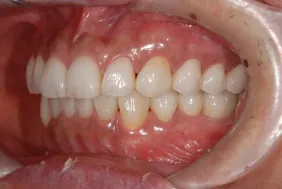

初診時

| 患者様のお悩み | 咀嚼障害、左の奥歯が抜けた。 |

|---|---|

| 治療法・使用素材 | インプラント治療の後、セラミック治療 |

| 患者様の年代 | 60代 |

| 治療開始年齢 | 60代 |

| 治療にかかった期間 | 1年6か月 |

| 性別 | 男性 |

| この治療のリスクについて | 歯ぎしりがひどいので修復物の耐久性が将来的に問題になる可能性があること |

| 治療にかかった費用 | 450万円 |